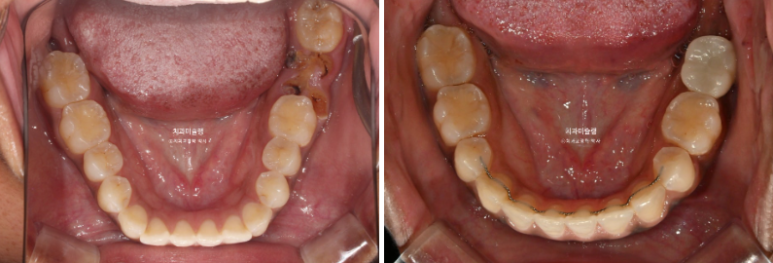

The patient had previously undergone non-extraction orthodontic treatment but did not wear retainers, resulting in relapse of the anterior teeth. Due to dental caries, several teeth were subsequently lost, leading the patient to seek re-treatment.

In the maxilla, one premolar had decayed to the point where only the root remained.

In the mandible, a molar was in a similar condition, with only the root remaining.

In cases where a premolar is missing like this, if protrusion or crowding is present, we can proceed as if premolar extraction had already been performed. By extracting other compromised premolars and utilizing the extraction spaces, we can resolve crowding and protrusion simultaneously. This approach is advantageous, as premolar extraction is often indicated in such cases, and it eliminates the need for implants.

On the opposite side, there was a tooth that had undergone root canal treatment and had been temporarily restored. We decided to extract this tooth.

For the mandibular arch, we decided to extract the second premolar affected by dental caries.